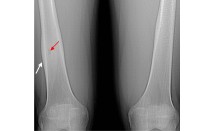

Fracture de fatigue du tibia